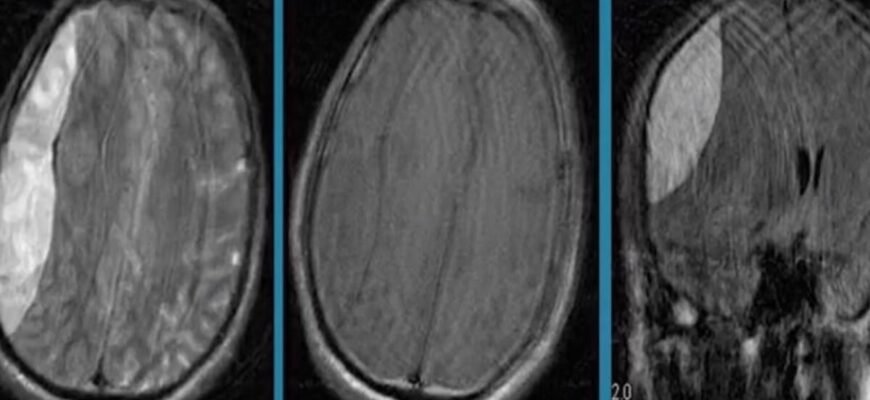

З діагностикою тут важливо діяти швидко. Як щось підозрюєте – звертайтесь до спеціалістів. Просто тримайте це в голові. Використовують рентген, комп’ютерну томографію (КТ) або магнітно-резонансну томографію (МРТ) для оцінки стану. І ось тоді – рішення. Складна операція? Може. Лікарські препарати? Авжеж, але залежить.